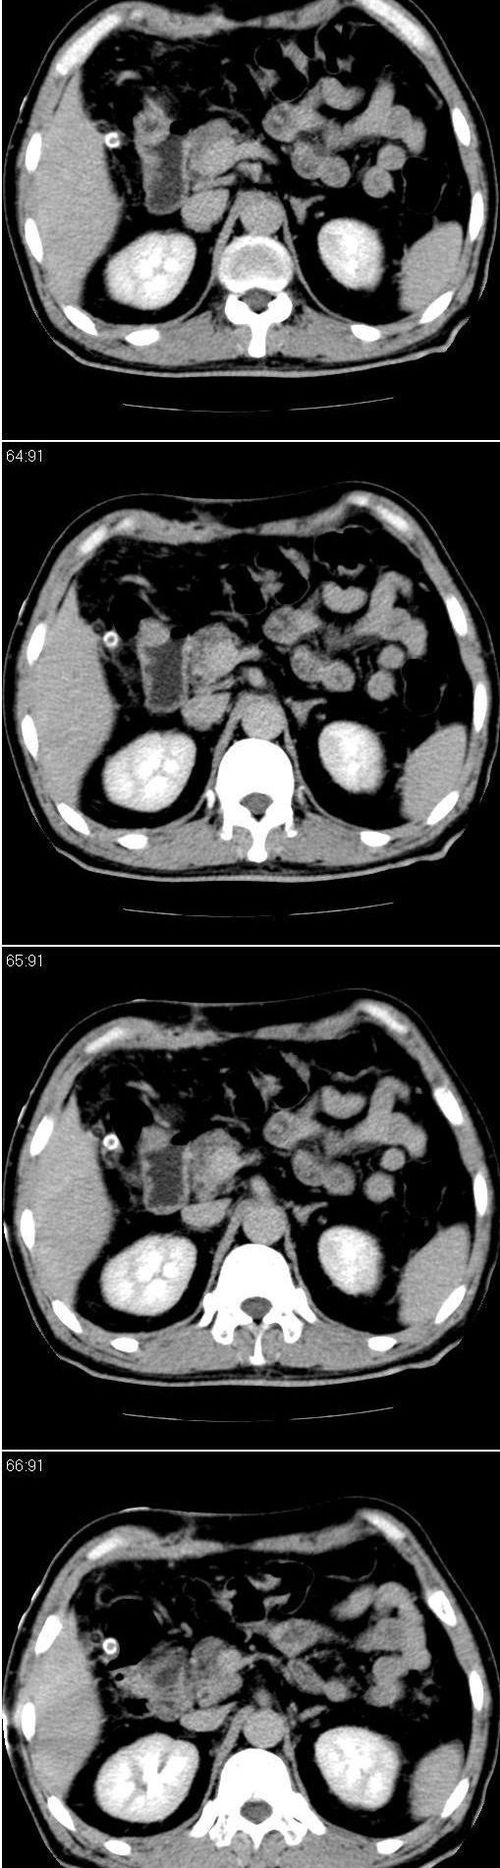

标题: CT13147:男,57岁。因胆结石阻塞性黄疸入院。 [打印本页]

标题: CT13147:男,57岁。因胆结石阻塞性黄疸入院。

男,57岁。因胆结石阻塞性黄疸入院。这是胆囊切除术后的照片,看看此片到底有什么问题。

肝内外胆管轻度扩张,胆囊窝内见引流管考虑胆囊切除术后改变.胃窦部软组织似增厚,建议胃镜检查.

支持 肝内外胆管轻度扩张,胆囊窝内见引流管考虑胆囊切除术后改变.胃窦部软组织似增厚,建议胃镜检查.

肝内外胆管轻度扩张。楼主提示左右肝管合汇区域壁稍厚。胆总管末段壁似也稍厚有轻度强化。就现有资料诊断难。